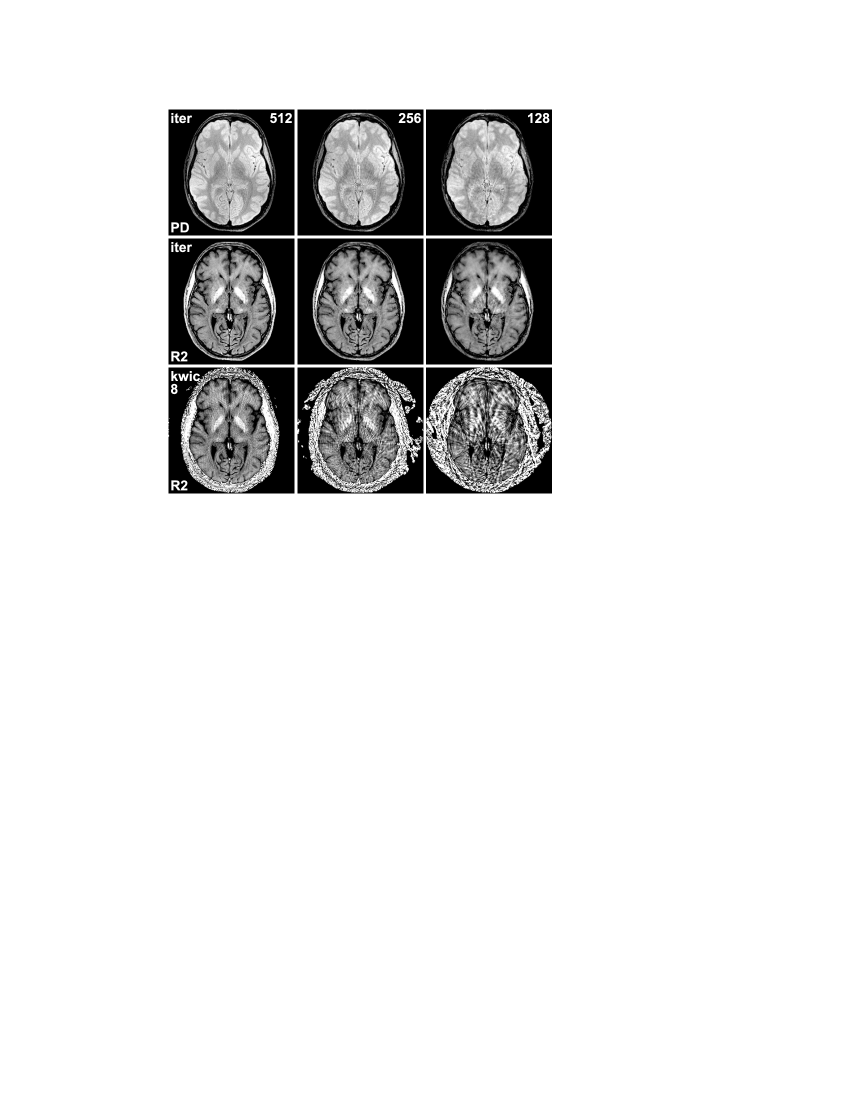

Figure 4: Spin-density maps (PD) and relaxivity maps (R2) estimated using the iterative approach for a transverse section of the human brain in vivo from (left) 512 spokes acquired with 32 repetitions, (middle) 256 spokes acquired with 16 repetitions, and (right) 128 spokes acquired with 8 repetitions (16 echoes each, base resolution 224 pixels, FOV 208 mm, bandwidth 360 Hz/pixel). The bottom row shows relaxivity maps obtained from the same data using the KWIC approach (kwic8).

Finally, Fig. 4 shows iterative reconstructions of the human brain from radial data with different degrees of undersampling, ranging from a total of 512 spokes (32 repetitions) to only 128 spokes (8 repetitions). As expected, the data reduction is accompanied by some loss of image quality, but even for 128 spokes the iterative approach still offers a relatively good separation of proton density and relaxivity. For comparison, relaxivity maps obtained by the KWIC approach are shown in the bottom row, and it can be seen that the image quality breaks down for higher degrees of undersampling.